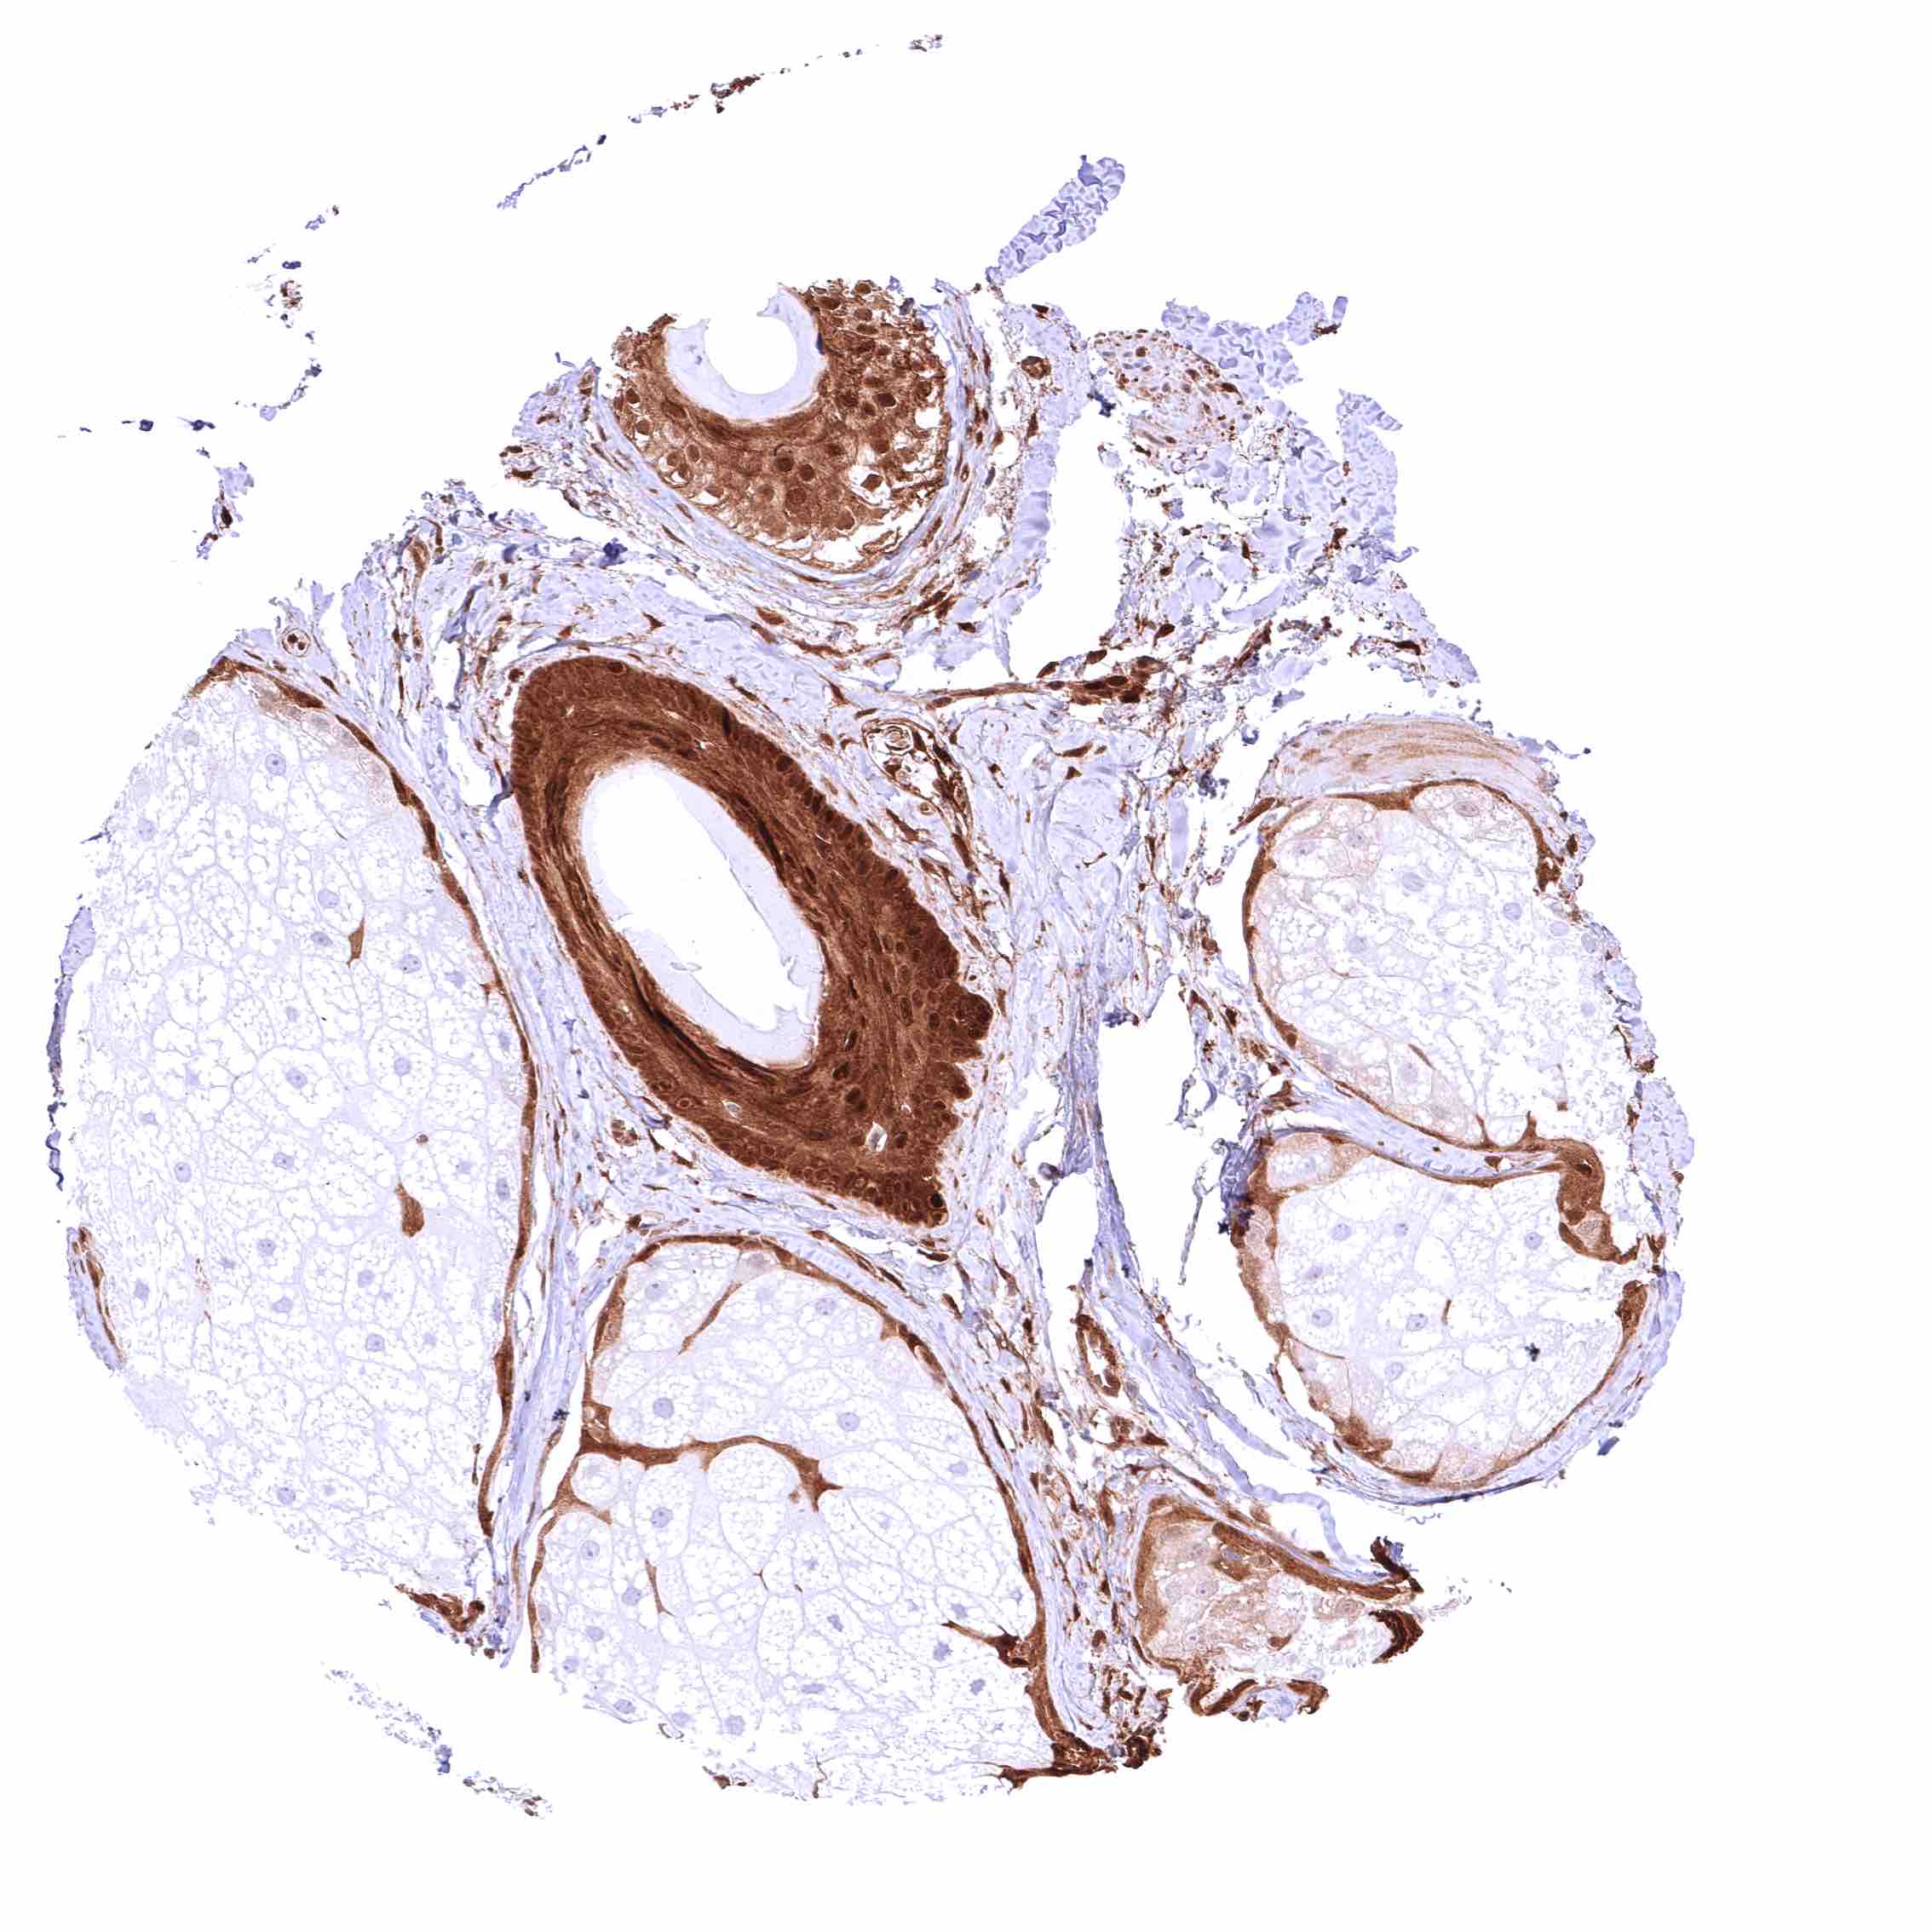

Skin, hairfollicle and sebaceous glands – Strong GSTP1 positivity of hair follicles and peripheral germinative cells of sebaceous glands while sebaceous cells remain GSTP1 negative.